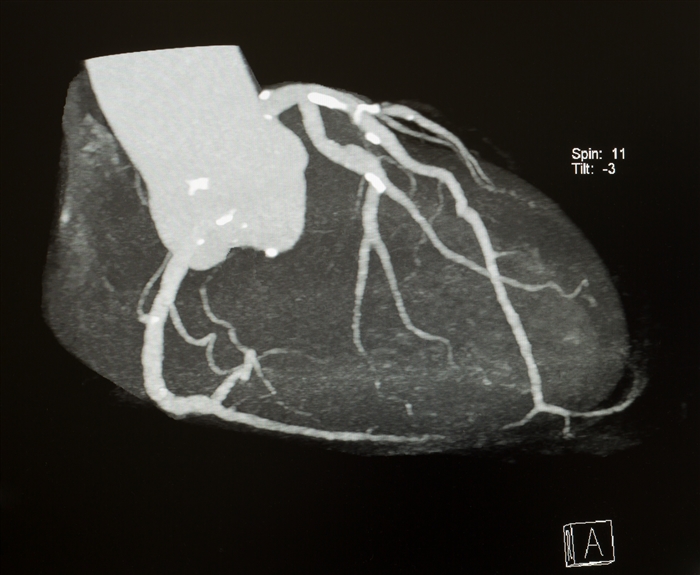

心臓CT

心臓CTでわかること

冠動脈CTとも呼ばれるように、

狭心症や心筋梗塞の原因となる

冠動脈の動脈硬化をみつける

ことができます。

動脈硬化が強い部位では石灰化(せっかいか)

といって、血管にカルシウムがつきます。

下の画像では血管が特に白くなっている

部位が石灰化です。

↓心臓CTで撮影した冠動脈(かんどうみゃく)。動脈硬化で血管についたカルシウムが白くみえます。

| CT(シーティー) | 冠動脈(かんどうみゃく)CTとも呼ばれ、心臓の大事な血管である冠動脈を調べます。X線を使います。 |